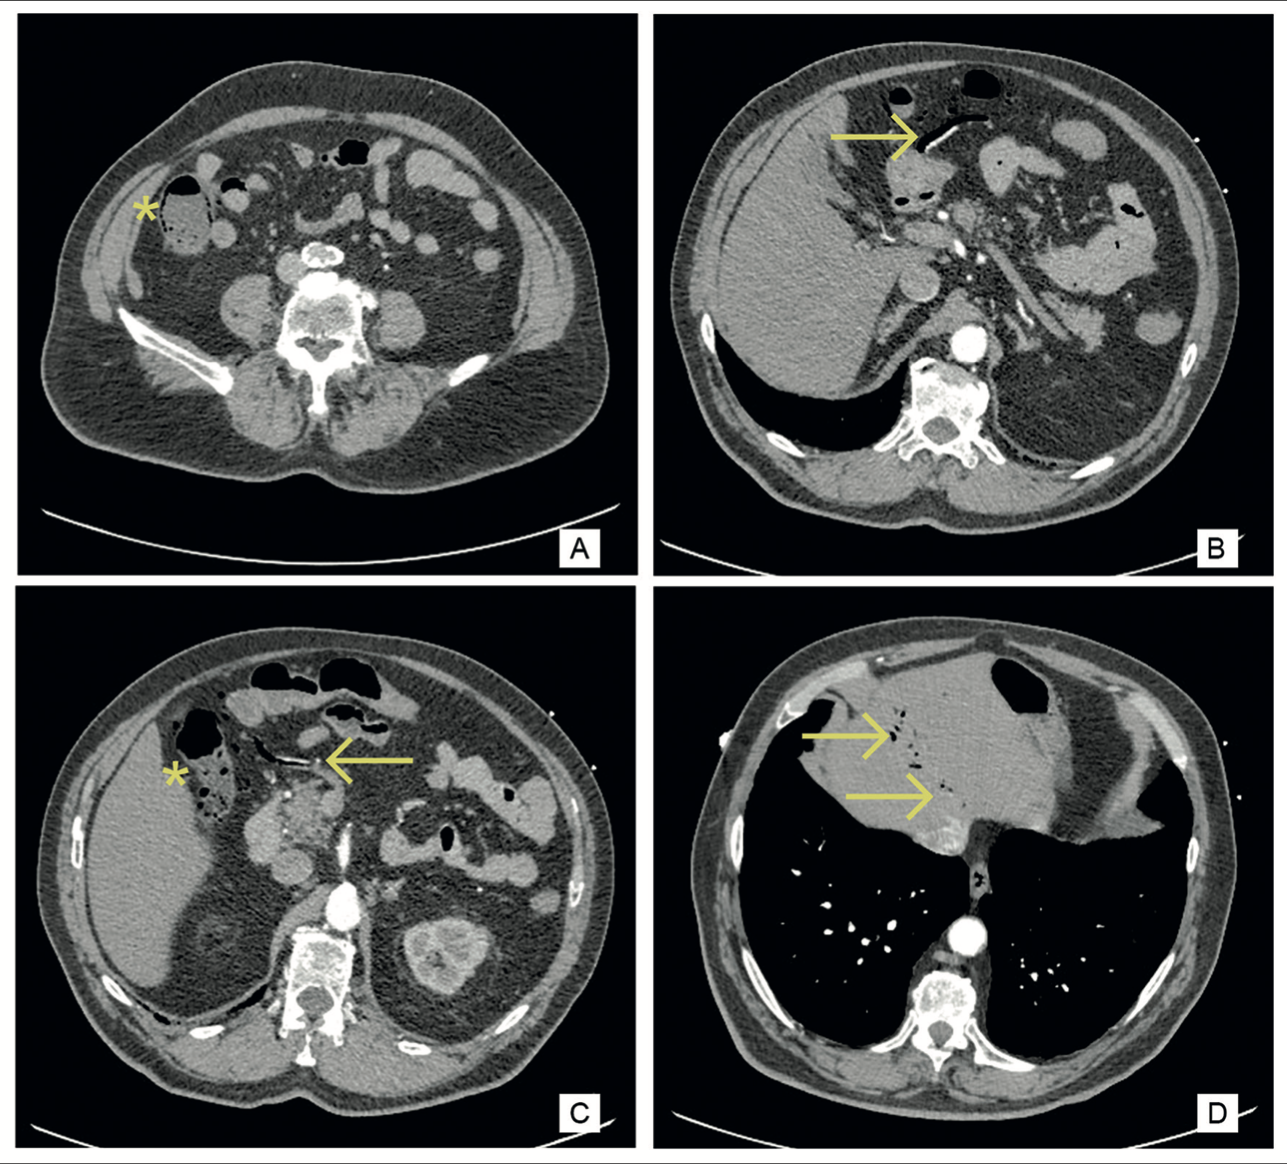

Alberto Perez Castilla, jorge arche prats